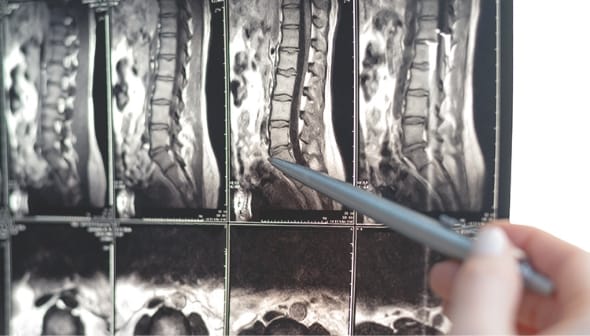

後遺障害の立証

後遺障害診断書には、症状をもれなく記載し、医学的根拠を丁寧に記載してもらいましょう。後遺障害を認定するために必要な検査がなされていない場合には、こちらから医師に検査を依頼する必要があります。後遺障害診断書や画像所見、検査所見などの手持ちの資料では不足する場合、意見書、陳述書などを作成して補強します。

後遺障害の認定に不服がある場合、異議申立をすることができます。異議申立の理由を記載した書面、追加資料を自賠責保険会社に提出します。ここで重要なのは、「なぜ後遺障害非該当とされたのか?」を分析し、医学的証拠を補充することです。医師の意見書、画像鑑定書等を準備し提出します。